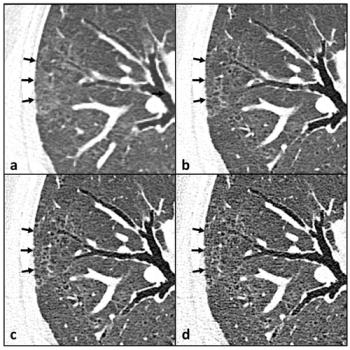

Researchers showed that adjunctive use of a deep learning algorithm resulted in an eight percent increase in sensitivity and a nearly 10 percent increase in specificity for differentiating between colon carcinoma and acute diverticulitis on computed tomography (CT) scans.